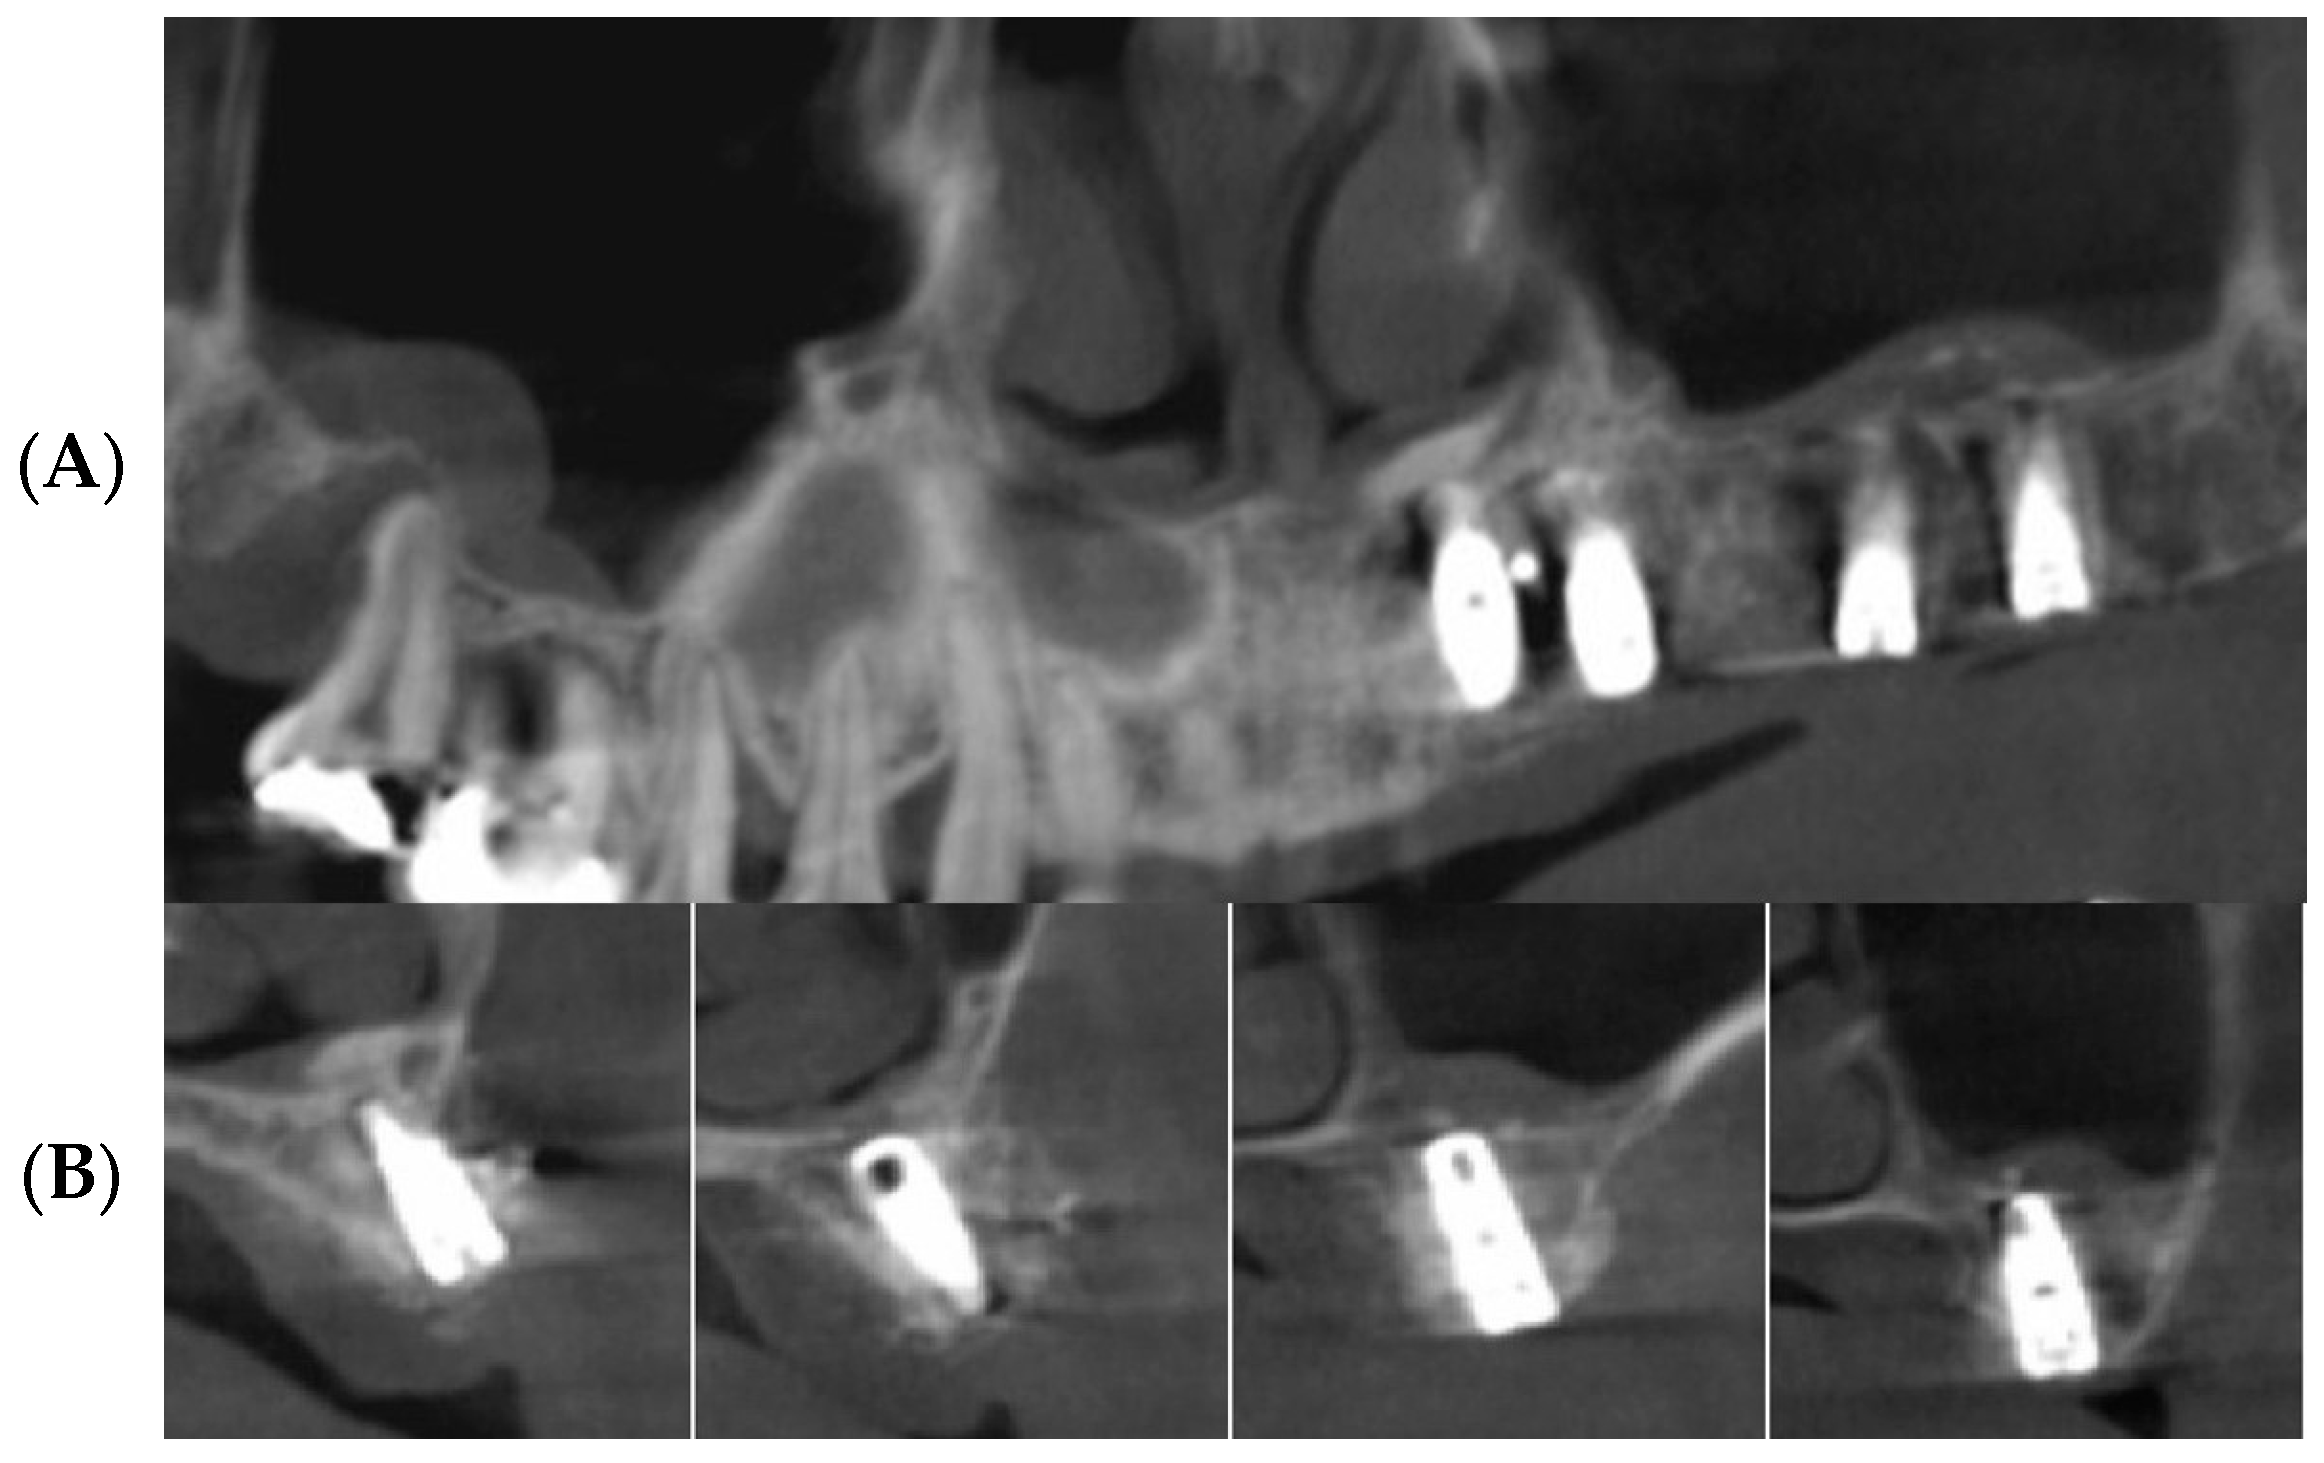

3.1. Clinical Results

3.2. Radiographic Results